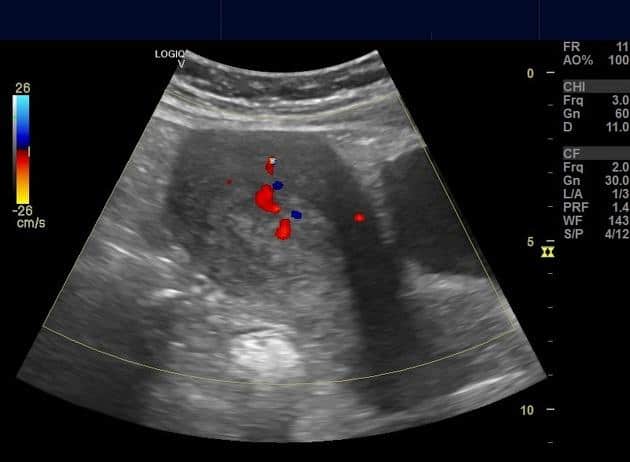

Polyp nội mạc tử cung

» Thông tin: Nữ giới – 40 tuổi.

» Lâm sàng: Rong kinh.